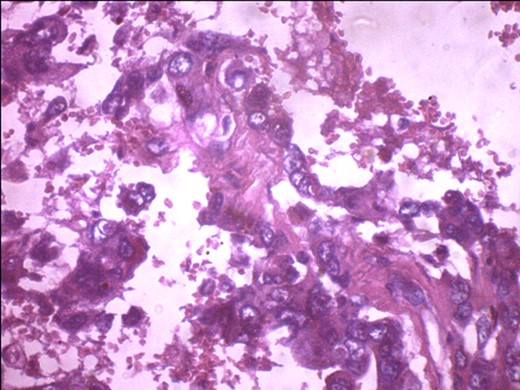

A 57-year-old woman presented with 5/12 history of left breast lump which gradually increase in size and became painful. Menarche was at 13 years without oral contraception. She had four confinements, the first being 20 years. Each child was breastfed for 8 months. No family history of breast cancer. Clinical examination showed breast asymmetry. Left breast was oedematous, shiny with extensive peau d'orange. Patient applied herbal preparations with multiple superficial skin excoriations. Outer quadrant breast mass was 8 cm, hard, with attachment to skin and underlying structures. No palpable axillary lymph node was felt and axillary ultrasonography, though desirable, was not done. Liver was not enlarged. Chest X-ray and abdominal ultrasound scan showed no involvement. Initial breast biopsy revealed an infiltrating atypical spindled tumour with hyperchromatic nuclei, which was both S100 and tyrosinase-positive. Tumour fungated with a darkly pigmented surface despite two cycles of neoadjuvant doxorubicin-based chemotherapy. Left simple mastectomy (Fig. 1) and axillary sampling (Fig. 2) of the sentinel and another slightly enlarged node were done, revealed a triple-negative invasive ductal carcinoma (Figs 3–6), with melanocytic differentiation (Figs 7 and 8), positivity for S-100 and patchy positivity for tyrosinase, an enzyme involved in melanin formation from dihydroxyl phenyl alanine. Only the sentinel node was involved, with the other showing reactive changes. Core biopsy of the tumour had ductal elements and was triple-negative.

ER negativity for rabbit monoclonal antibodies. Few stromal cells are positive black.